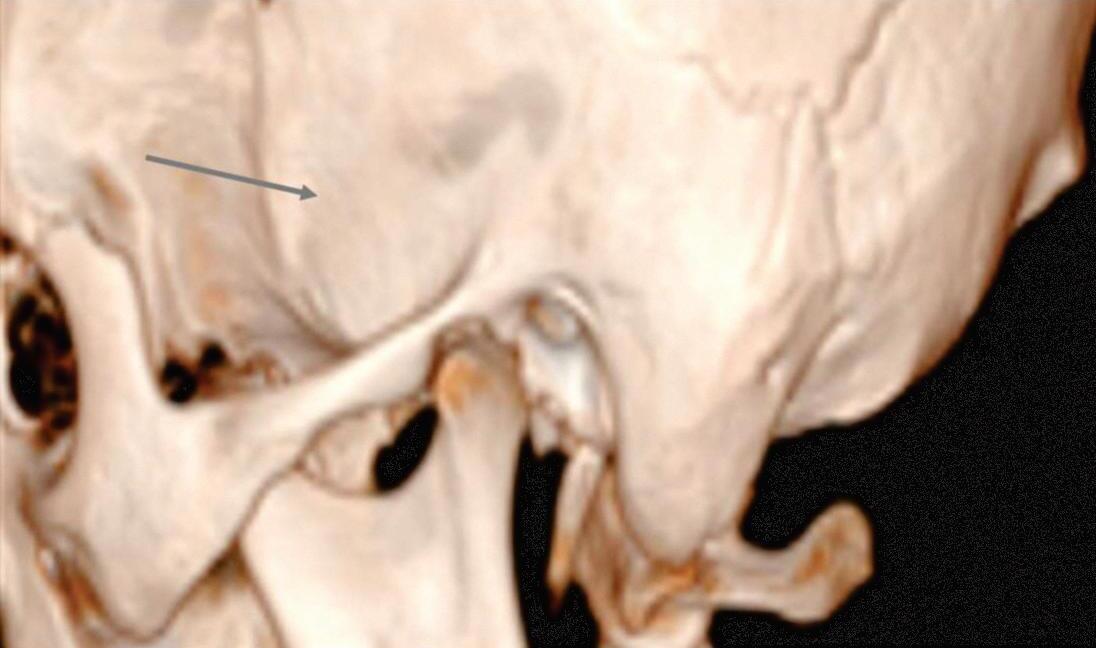

Existem diversas aplicações dos tomógrafos de múltiplos detectores na avaliação do osso temporal, destacando-se a avalição

detalhada da cadeia ossicular no eixo de cada ossículo, melhor demonstração do posicionamento de próteses da cadeia ossicular, avaliação da integridade dos canais semicirculares através das incidências de Poschl e Stenvers. Além de possibilitar a obtenção

de reconstruções tridimensionais de alta qualidade, importantes no estudo das fraturas do osso temporal, malformações das orelhas interna e externa e relação das lesões da fossa posterior com estruturas da base do crânio (Figs. 1-2 a 1-9).

1-6. TC 3D: Osso temporal normal, visão superior e lateral. TC 3D visão superior (a) e lateral (b) do osso temporal normal (setas).